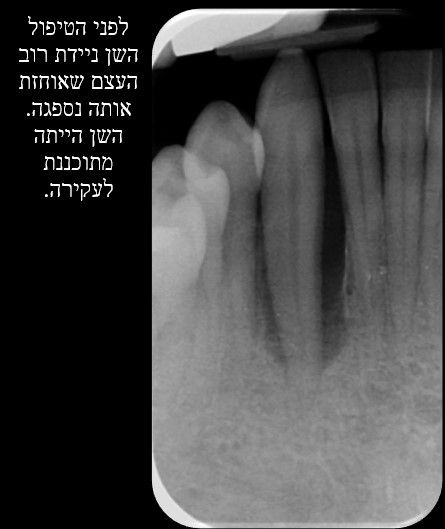

:הצלת שיניים אבודות

לפני טיפול